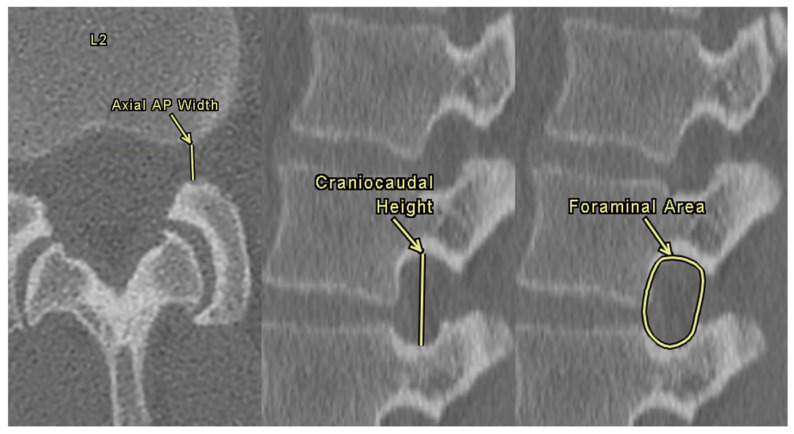

Methods: A retrospective chart review was performed on 852 patients who underwent CT imaging of the lumbar spine. ISD was measured from L1 to L5 as the shortest distance between the most caudal tip of the superior spinous process and the inferior spinous process. DSH was measured at the anterior, middle, and posterior margins. NFDs were assessed in axial and sagittal views, including axial width, craniocaudal height, and foraminal area. Statistical analysis assessed correlations between ISD, NFDs, DSH, and demographic variables.